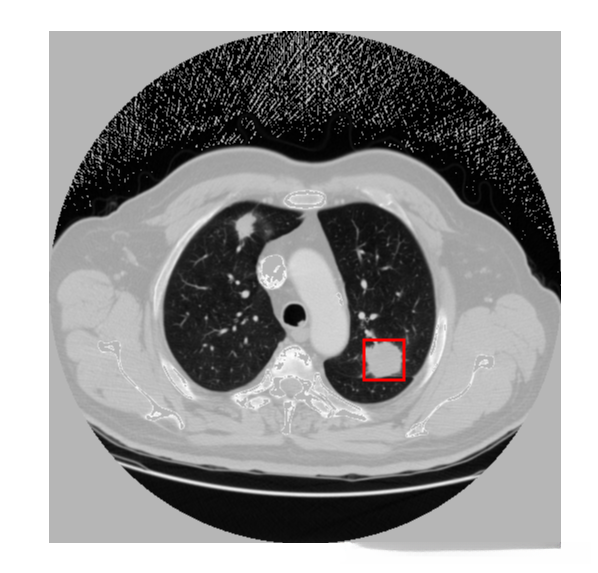

下图左边是预测,右边是根据标注生成的ground truth。

更新: 2019.9.23

修改anchor size后重新训练

基于标注生成的标注图像,在实际应用中无法获取到发现肺结节的bounding boxes大致呈现比例为1:1。然而,在yolov3算法中由于采用了3 个特征尺度来进行位置预测,在此处我们选择聚类中心的数量定为**3。

通过反复进行多次聚类运算,可以获得较为合适的anchor大小(但有时可能出现不收敛的情况,并导致计算出现问题):

这个之84.07%已经很高了,比voc 67%左右高出不少。

检测效果: